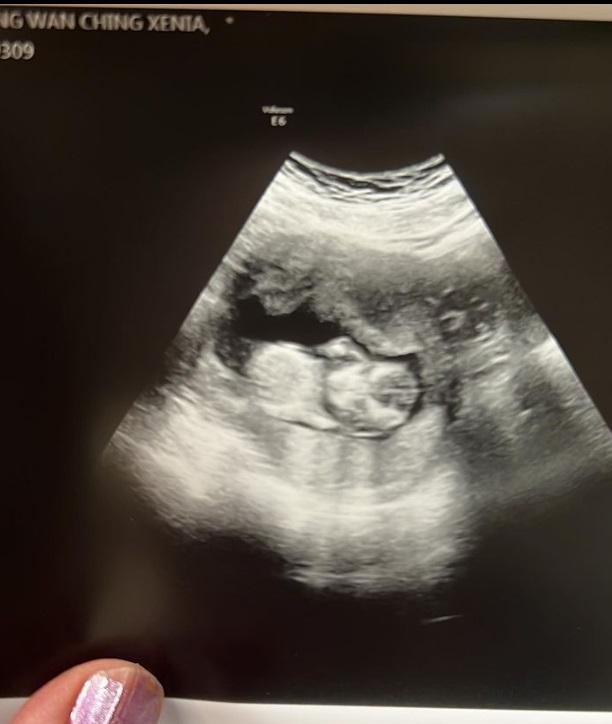

莊韻澄佗B四個多月,最後需要接受終止懷孕手術。

莊韻澄上月宣布懷有第二胎,惟今日傳來壞消息,她稱腹中的胎兒因為患上罕有的巴陶氏症,要在20週前終止懷孕手術,她上載印有女兒腳印的照片,留言不捨說︰「雖然我們緣份只有4個多月,但我仍然感受到懷著女兒的幸福,感恩你的到來讓我學習面對無常,永遠愛你的媽媽。」